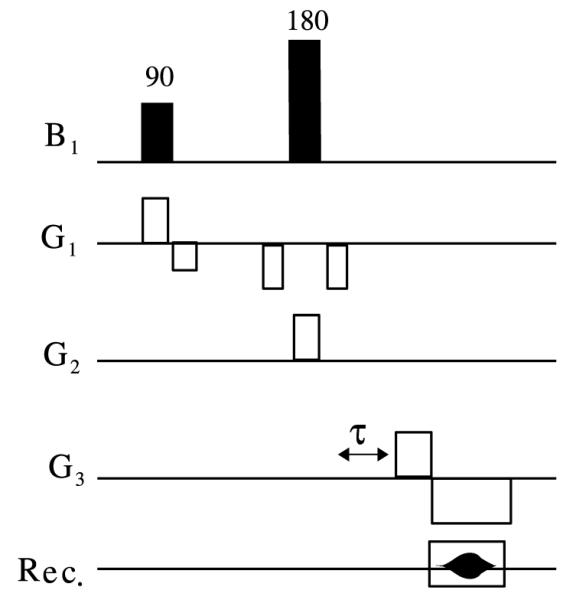

Unique determination of ηlm for all first and second-order shims is possible using information from a few carefully chosen linear field map projections. Such projections can be acquired using oblique slice selection to define rectangular columns and field-map readouts along these columnar directions. Fig. 7 outlines a pulse sequence for collection of such field-map projections [48].

Pulse sequence for acquisition of FASTMAP linear projection field map. G1, G2 and G3 represent orthogonal oblique gradient vectors defining a given projection. As was described in Section 3.1, acquisitions must be made with two different timing parameters τ (typically τ = 0 and τ > 0). A slice selective 90° pulse brings magnetization in a given oblique slice down to the transverse plane and a 180° pulse then operates on a second slice intersecting the first slice. Readout occurs then in a direction perpendicular to both slice selection gradients.